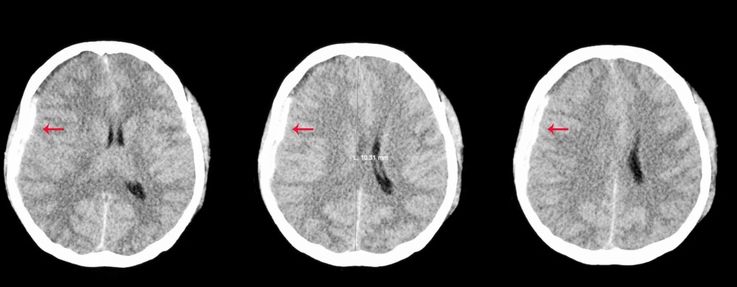

Diagnóstico por Imagem de Urgência

Ao notar alterações cognitivas ou motoras súbitas em um idoso, a investigação neurocirúrgica deve ser imediata. A Tomografia Computadorizada (TC) de crânio é o exame de escolha por ser rápido e eficaz, mostrando o hematoma como uma imagem em formato de “lua crescente” de densidade reduzida. A Ressonância Magnética também pode ser utilizada em casos de dúvida para identificar coleções sanguíneas em diferentes estágios de evolução.